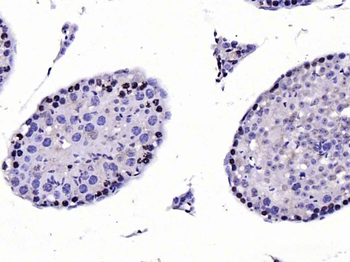

CDKN1A Antibody

Catalog Number: orb682382

| Description | CDKN1A Antibody |

| Target | CDKN1A |

| UniProt ID | P38936 |